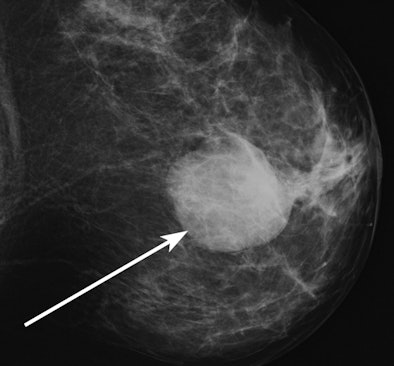

![]() |

| Mammographic image of a high-density mass (arrow). |